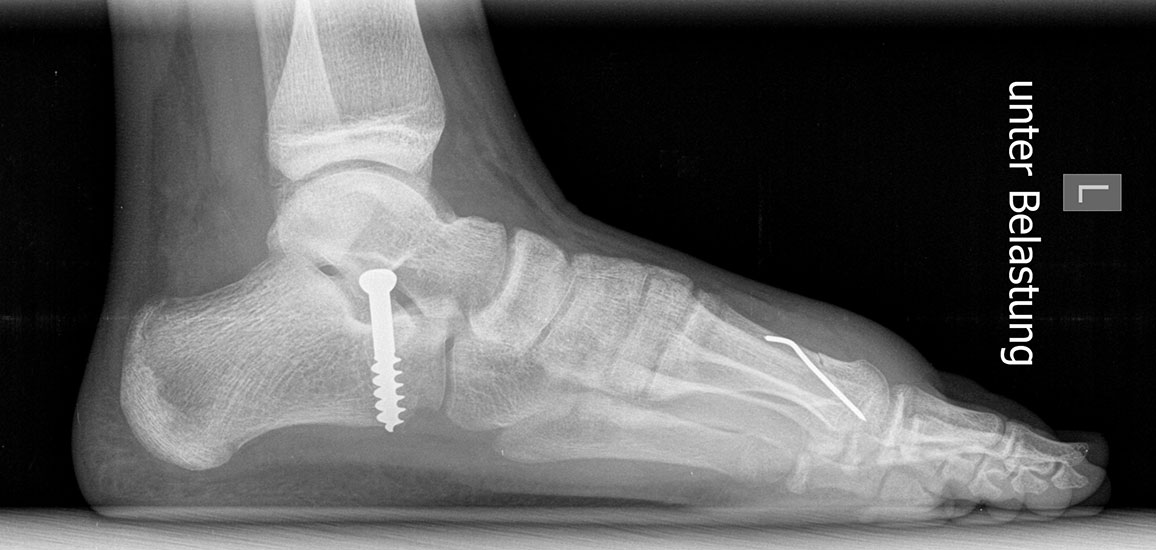

Röntgen

Standard ist die belastete Röntgenaufnahme des Fußes dorso-plantar und seitlich. Günstig ist eine Röhrenkippung von 10°-20°, um die Gelenke der Lisfranc-Linie einsehen zu können.

• Nach Schluss der Wachstumsfugen: TMT I Arthrodese nach Lapidus 2425